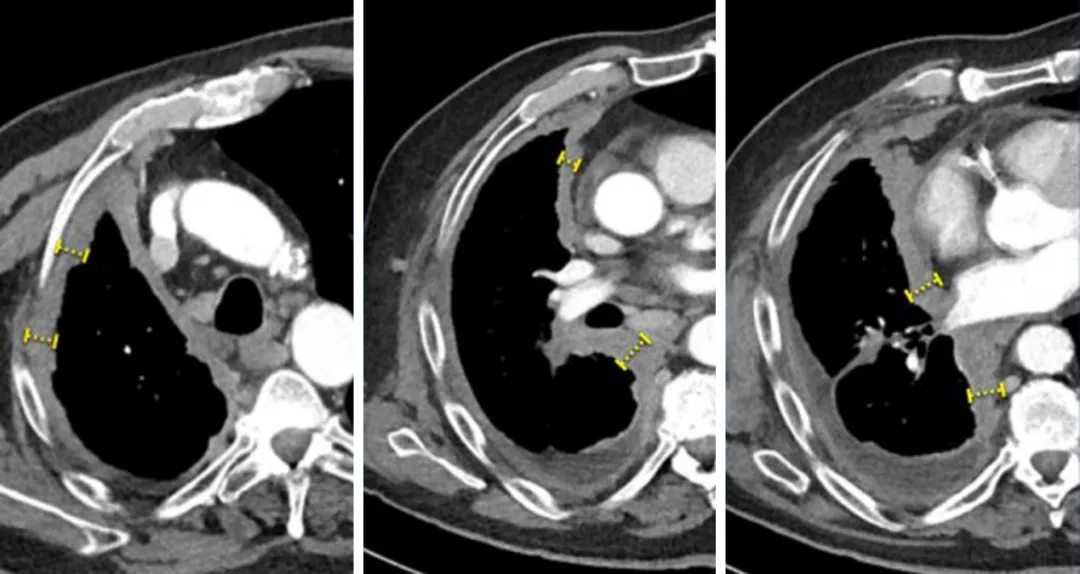

依靠测量最长直径来评估肿瘤疗效有个特殊情况,就是恶性胸膜间皮瘤,由于该肿瘤一般呈非球形生长,这导致对其进行长轴测量来随访病变变得非常困难,因此,我们一般不测病变的最长径,而是测量垂直于胸壁的肿瘤厚度,研究证实该测量值与肿瘤疗效有很好的相关性,通常推荐在三个不同层面的两个位置测量垂直于胸壁或纵隔的肿瘤厚度。

一名69岁男性恶性胸膜间皮瘤患者的增强CT图像,根据RECIST1.1测量恶性胸膜间皮瘤,在三个不同层面的两个位置测量垂直于胸壁或纵隔的肿瘤厚度,并且最好在上胸部层面进行测量。